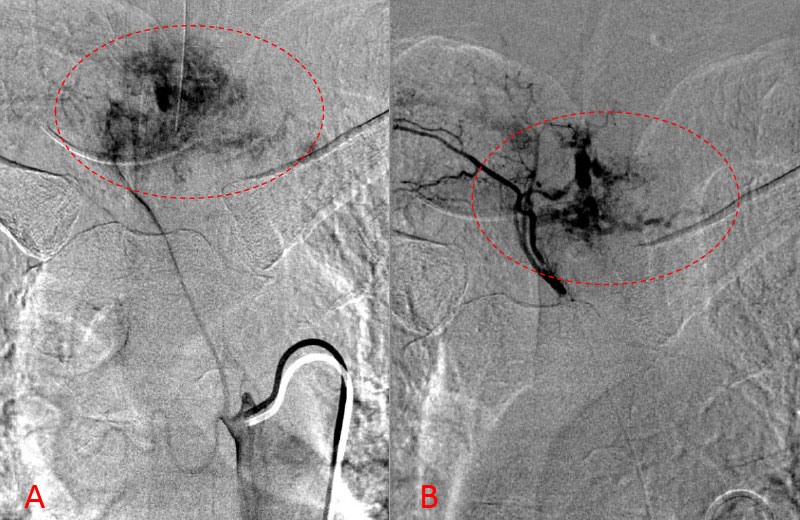

He presented to the emergency room with a one-week history of thoracic pain in addition to bilateral lower extremity weakness and paraparesis. MRI imaging with contrast showed a diffuse abnormal signal within the vertebral body of T3 and the posterior elements with lobulated soft tissue lesion extension into both paraspinal areas (Figure 1. A, B, C).

Figure 1. A) Sagittal T2 MRI demonstrates aggressive hyperintense T3 hemangioma involving the body and posterior elements compressing the thoracic spinal cord (arrows)

Figure 1. B and C) Axial MRI images of T3 demonstrates extensive infiltrative lesion with extradural compression of the thoracic spinal cord. (Dashed lines in A) tumor infiltration; Dashed lines and Arrows in B) cord compression.